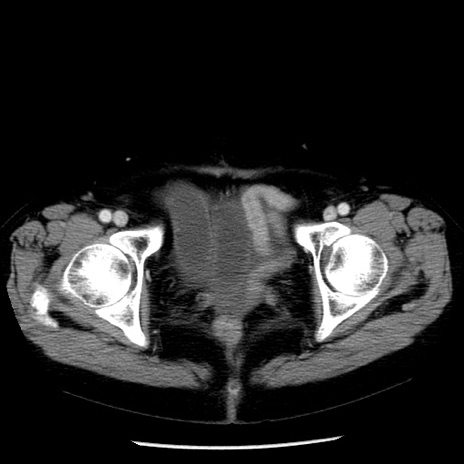

冠状断像

【症例】70歳代女性

【主訴】腹痛、嘔吐

【現病歴】15時間程前(昨晩)より腹痛あり。今朝になっても症状の改善なく、嘔吐あり。腹痛も増悪あり、救急外来受診。

【既往歴】子宮癌全摘術後

【身体所見】意識清明、BP 121/72mmHg、P 74bpm、SpO2 100%(RA)、腹部:平坦・軟、腸雑音ほぼ聴取せず。下腹部・心窩部・臍左上に圧痛あり。反跳痛なし。

【データ】WBC 10600、CRP 0.15